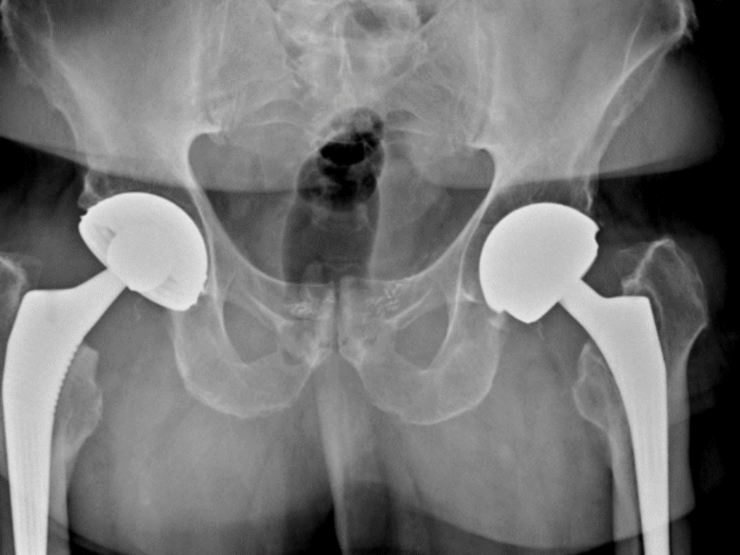

Le bassin est creusé d’une cavité arrondie appelée cotyle (ou acetabulum) dans laquelle s’articule l’extrémité supérieure sphérique du fémur appelée tête du fémur. Un joint appelé labrum, de consistance élastique assez ferme, coiffe le pourtour de la cavité et participe à la stabilité et la coaptation de l’articulation.